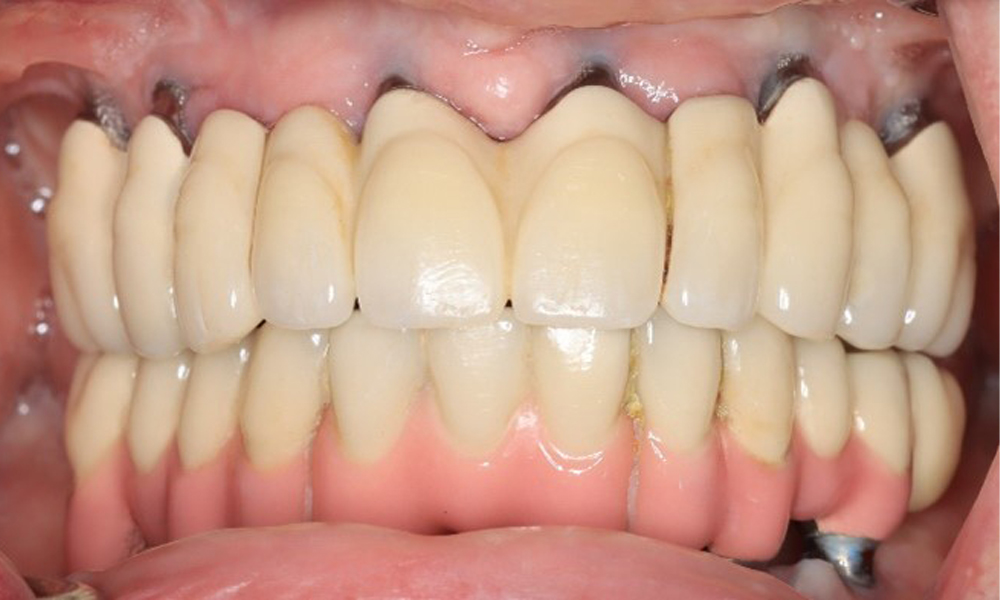

Frontansicht Gebiss (Ober- und Unterkiefer)

Abb. 3: Frontansicht

Eine 74-jährige Patientin stellt sich in der Sprechstunde vor. Die Anamnese zeigt, dass die Patientin gut eingestellten Bluthochdruck hat und Lixiana einnimmt. Weiterhin hatte die Patientin im Jahr 2020 ein Nierenkarzinom. Die Lebensgewohnheiten der Patientin sind unauffällig. Die Patientin hat keine eigenen Zähne mehr. Sie hat im Oberkiefer und Unterkiefer jeweils sechs Implantate, die mit Kronen bzw. über Brücken versorgt sind. Anhand der aktuellen Befunde lässt sich keine periimplantäre Mukositis bzw. Periimplantitis feststellen; vereinzelte (geringfügige) Blutungen an den Implantat(-versorgungen) liegen vor.